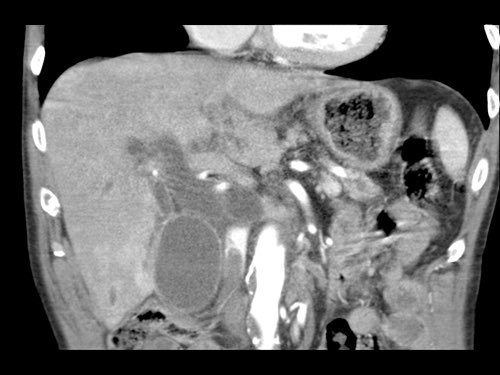

Ở những bệnh nhân dự kiến phẫu thuật tụy, điều quan trọng là cần đặc biệt chú ý tìm kiếm nguyên ủy bất thường của động mạch gan phải hoặc động mạch gan chung.

Các động mạch này xuất phát từ phía phải của động mạch mạc treo tràng trên (SMA) và đi qua vùng lân cận đầu tụy, làm tăng nguy cơ xâm lấn của khối u hoặc tổn thương do phẫu thuật.

Tần suất được ghi nhận của các bất thường đặc hiệu này lần lượt là 11-21% và 0,5-5%.

Các hình ảnh mặt phẳng đứng ngang của một bệnh nhân có khối u ở đầu tụy và động mạch gan phải phụ thêm.

Lưu ý sự áp sát của động mạch phụ thêm bởi khối u.